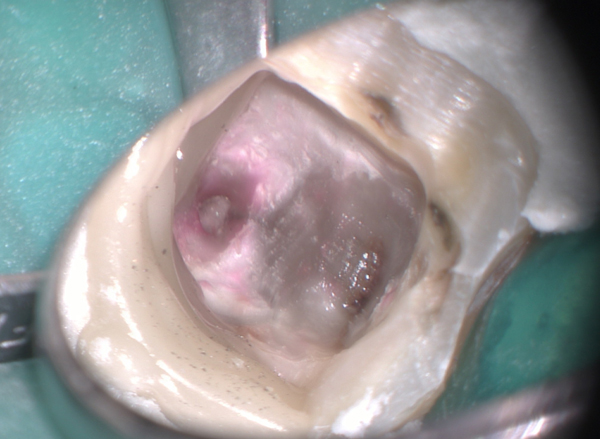

下顎7番。ピンクがかっているのはう蝕検知液を使ってむし歯を除去しているからです。感染根管です。

この歯の根管口を明示して器具が直線的に入るように形成したのが下の写真です。ストレートラインアクセスを確保した状態です。